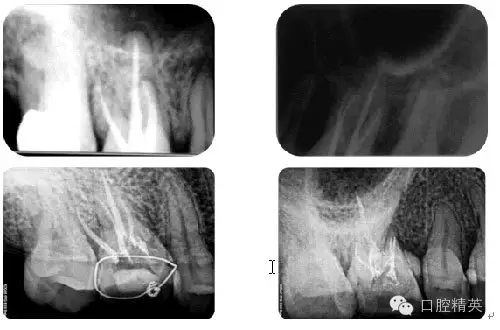

病例2:各型MB2根管

病例3:C型根管

病例4:根管再治療